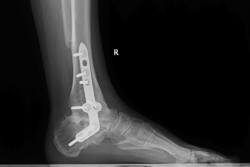

Figura 1. Fractura conminuta de la cúpula del astrágalo.

Se trata de un paciente varón de 35 años que, tras una precipitación, presenta impotencia funcional en el miembro inferior. Tras la valoración clínica y radiológica, se observa un estallido de la parte posterior de la cúpula astragalina (Figura 1).